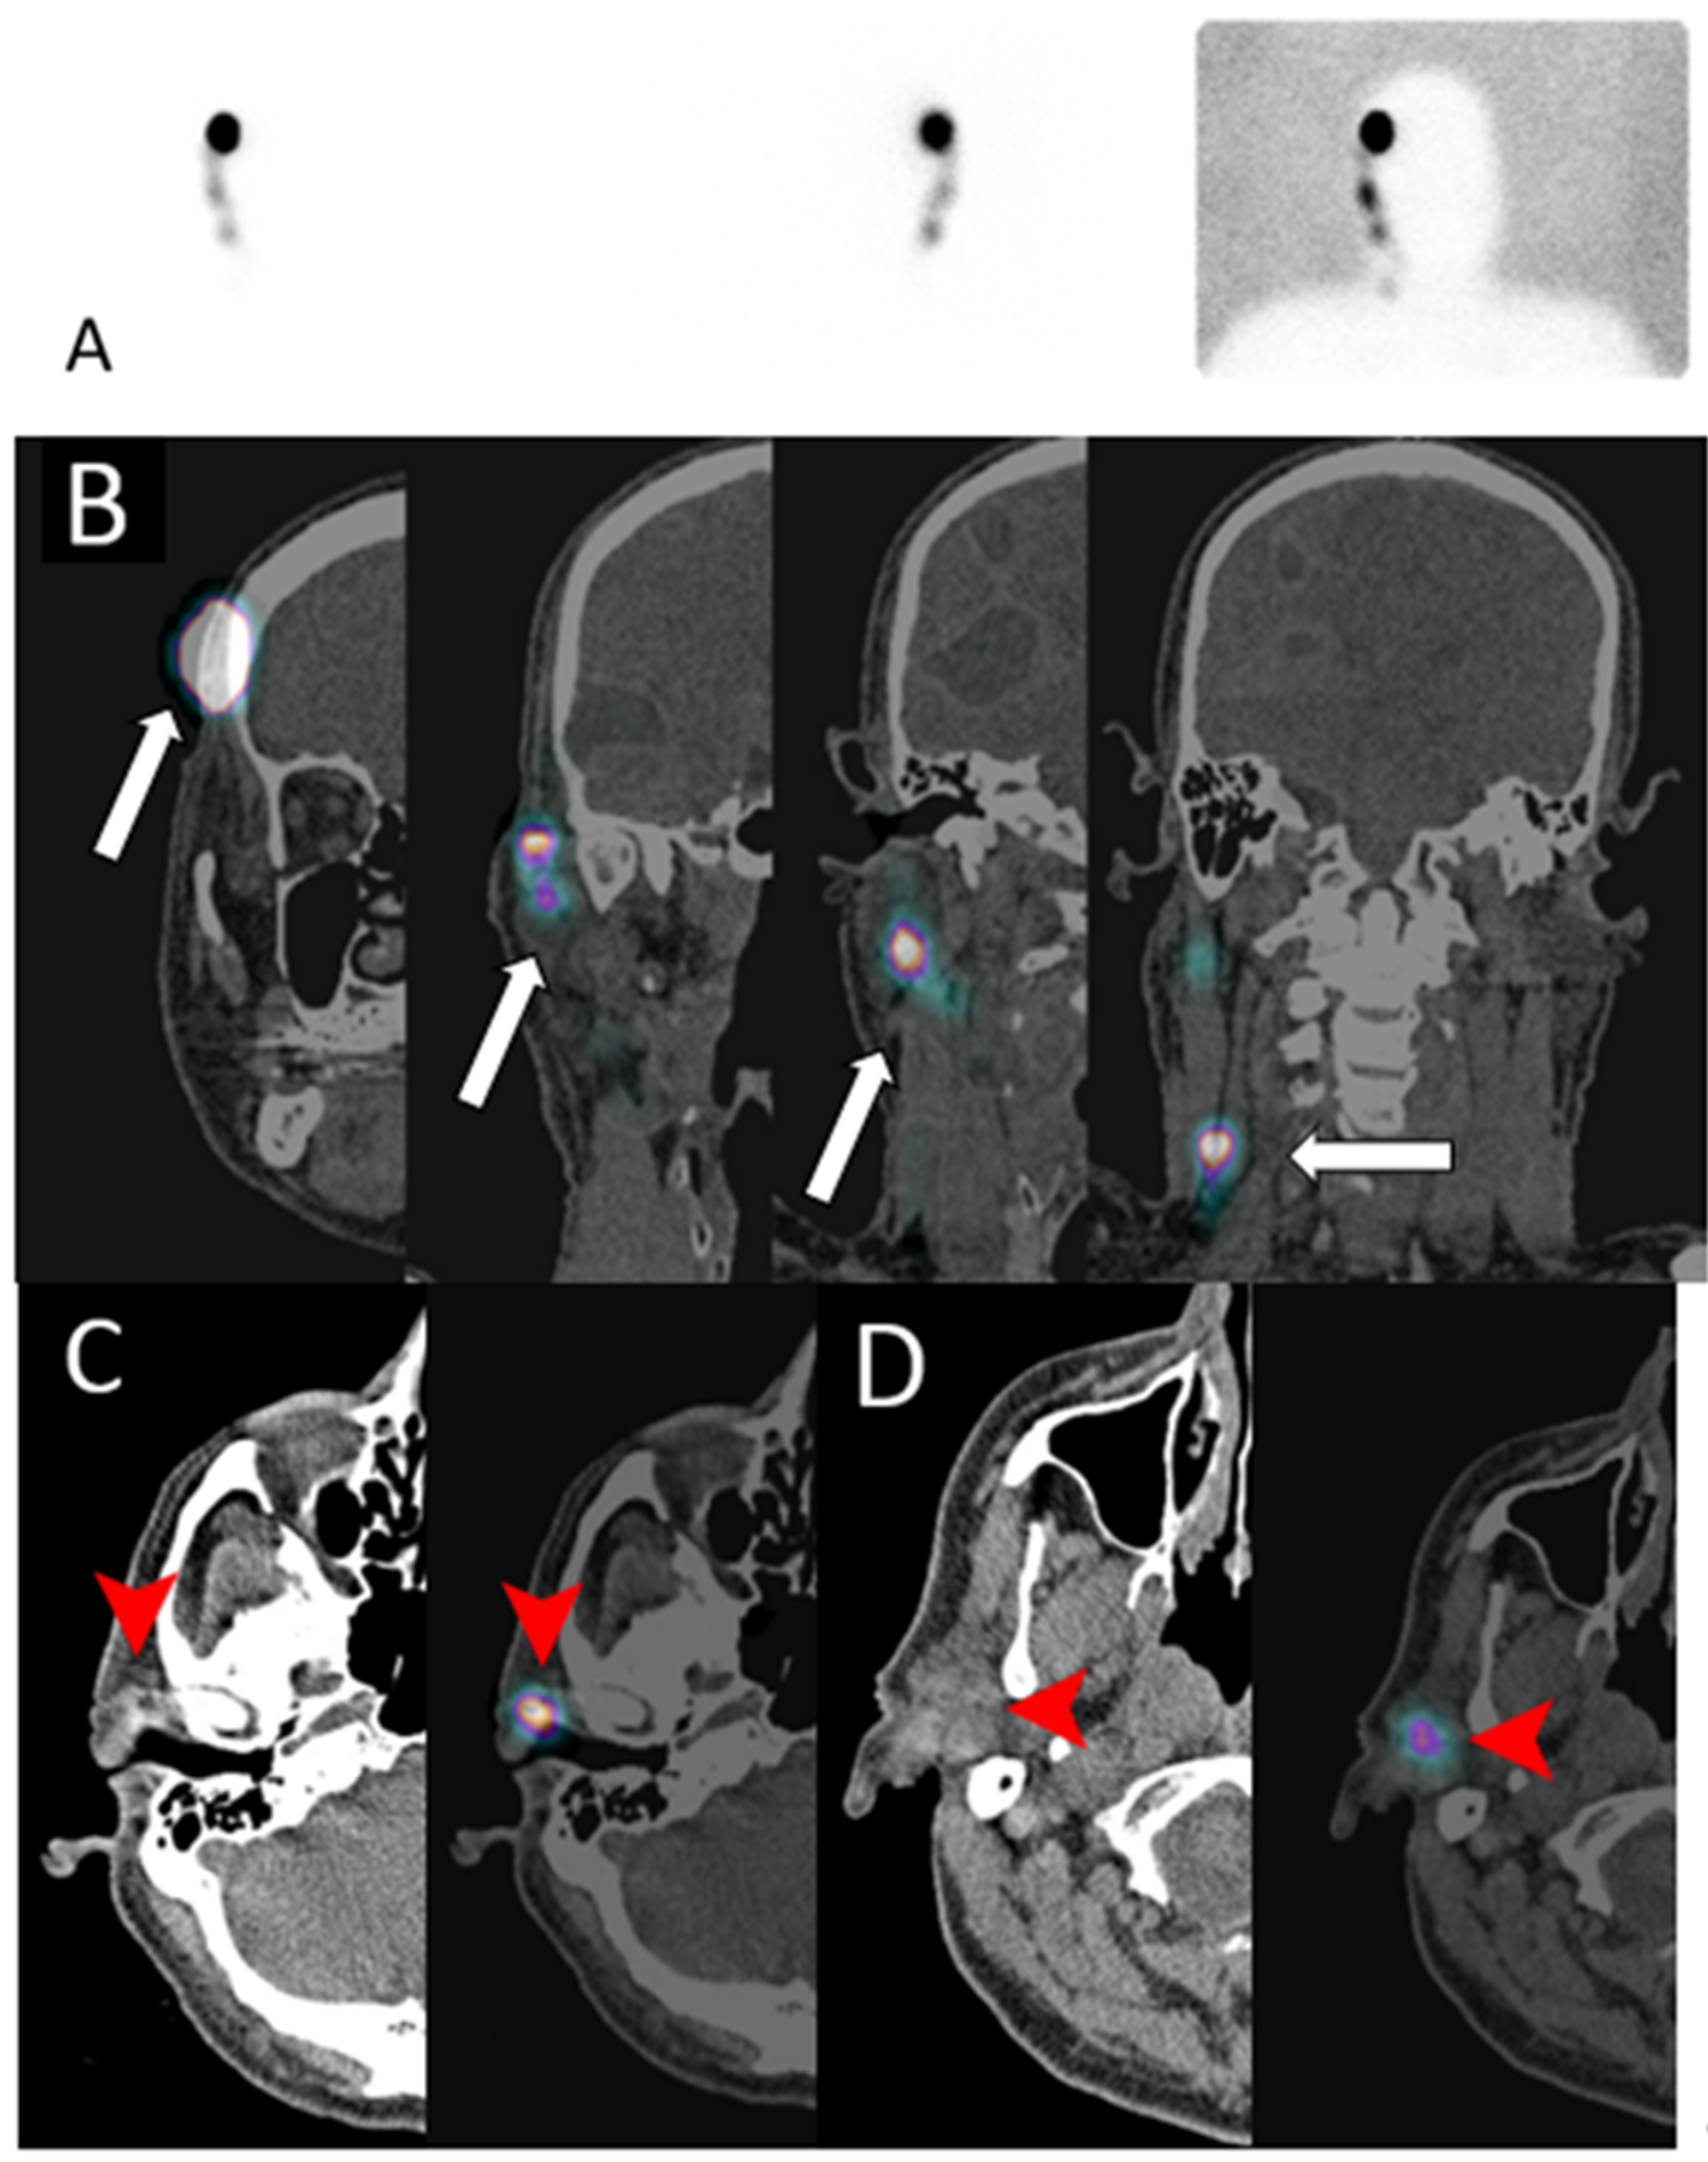

Lymphoscintigraphy